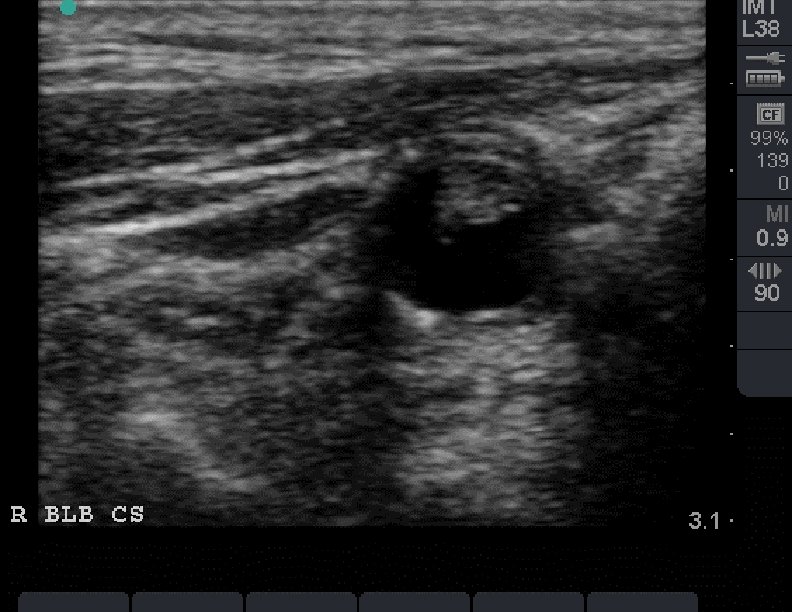

Heterogeneous Plaque

Heterogeneous Plaque Longitudinal view